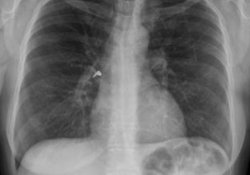

Была на консультации в пульмонолога и в то время начался приступ. После осмотра меня и флюорографического снимка он сказал, что легкие у меня здоровые и если б не увидел приступ, то он бы не поверил моей болезни.